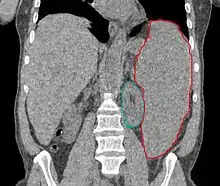

- Retrospective. 22 courses for 19 patients. Total dose 1.5 - 8.0 Gy (median 4.5 Gy), fractional dose 0.25 - 1 Gy delivered weekly or twice weekly. AP/PA. Median field reduction 25%

- Retrospective. 22 patients with 32 courses of SI. RT 0.25 - 0.5 Gy/fx, fields AP/PA and decreased with response, treatment halted with response